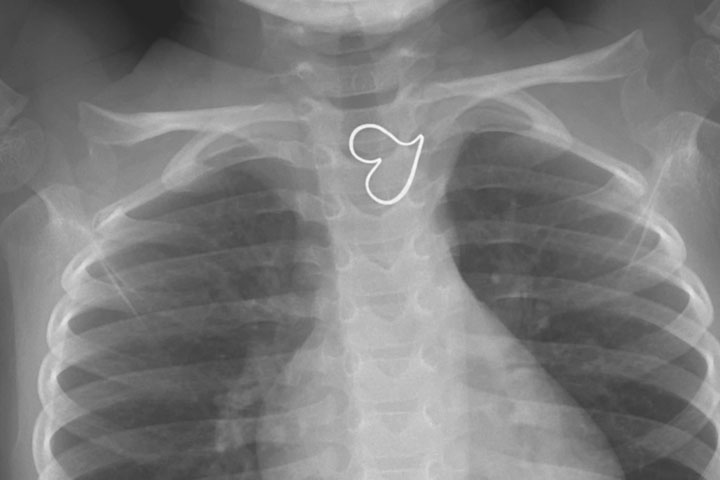

After taking antibiotics for week i recovered. Honor Society of Nursing STTI X-rays are often used to detect if throat cancer is your throat disorder. Shocking X-ray shows button battery lodged in throat of 11-month-old girl which was stuck there for FOUR MONTHS and caused her to reject food before it was removed by surgeons January 13 2021 Read Toddler Sofia-Grace Hill swallowed a watch battery the size of a 10 pence piece.

Toddler S Heart Of Gold Shows Up On X Ray National Globalnews Ca